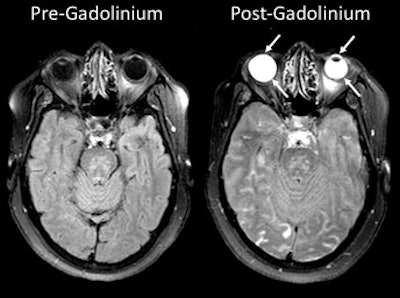

"The fluids in the eye are similar in terms of their properties to CSF, so they also are suppressed on the FLAIR scan," Leigh explained. "We started to notice that when gadolinium would leak into the brain, it would also sometimes leak into the eye, causing the fluid in the eyes not to suppress; the eyes would become bright. We weren't quite sure what to make of it, and that's why we embarked on this study."

MRI scans show gadolinium leakage in the eyes after the contrast agent is administered to a stroke patient. Images courtesy of the NINDS.Regarding the influence of tPA, gadolinium was present in 86 patients (79%) who received it and in 41 patients (71%) who did not. There was no statistically significant association between the administration of tPA and the occurrence of gadolinium leakage (p = 0.695).